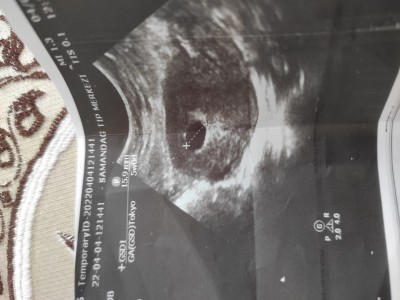

image Yolkkesesi var mı tekrar bakabilir misiniz yeniden çektim

Gebelik haftası 5+ 5

Yolk kesesi, vajinal ultrason da gebelik kesesi 8-10 mm, karından ultrason da ise 20 mm boyutuna geldiğinde görülebilirmiş. Gebelik kesenin boyutuna göre bilinenler.

Bunlarla ilgili hiç bir bilgim olmadığı için soramadım sadece kesen güzel büyümüş bir hafta daha bekleyelim dedi

Kese düzenli büyümüşse korkma gebelik saglikli ilerliyo

Kese güzel büyümüş  dedi ama  bebeği göremeyince çok huzursuz oldum

O haftada bende de bebek gozukmuyodu 7. Haftada bebegi gördüm